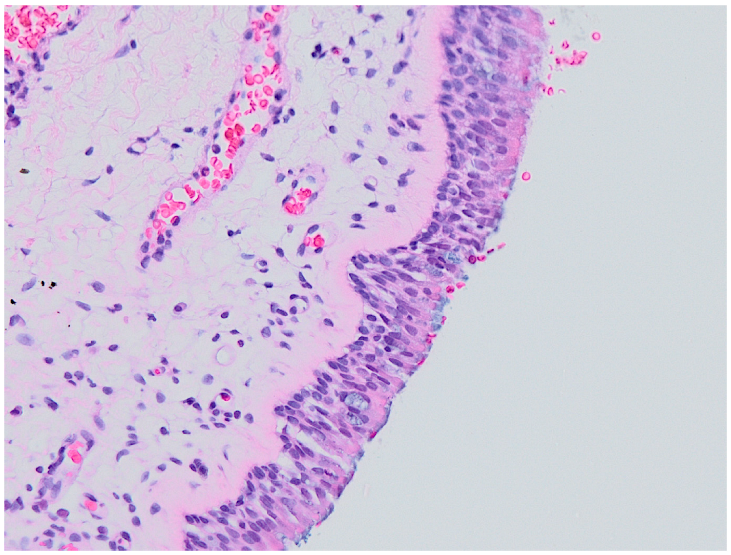

- 0

- Normal histology (no inflammation);

- 1

- Epithelial hyperplasia;

3.2. Histology

3.3. Correlation of Histology and Detected Compounds